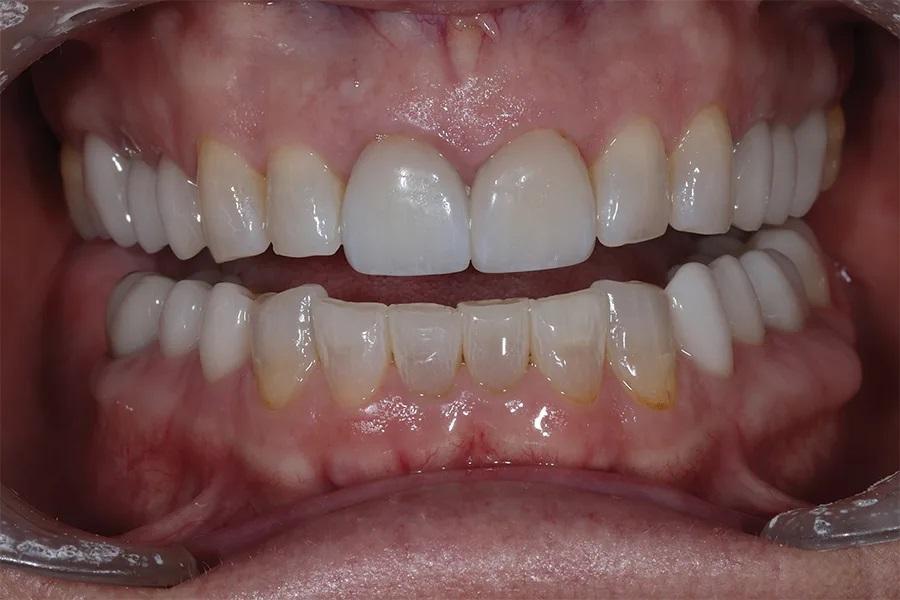

Фото 9. Крупный план с установленными реставрациями в боковых отделах. Новый ВРО отчетливо визуализируется: режущие края верхних зубов располагаются выше фасеток износа на вестибулярной поверхности нижних резцов.

Фото 10. Вид реставраций боковых зубов после лечения при ретракции, демонстрирующий расширение буккального коридора.

Окклюзия была повторно проверена, откорректирована и отполирована. Были достигнуты одновременные, двусторонние и равномерные по интенсивности контакты в области боковых зубов (фото 9 и фото 10). Пациентке был назначен повторный прием через 1 месяц для оценки окклюзии с точки зрения функции и комфорта.